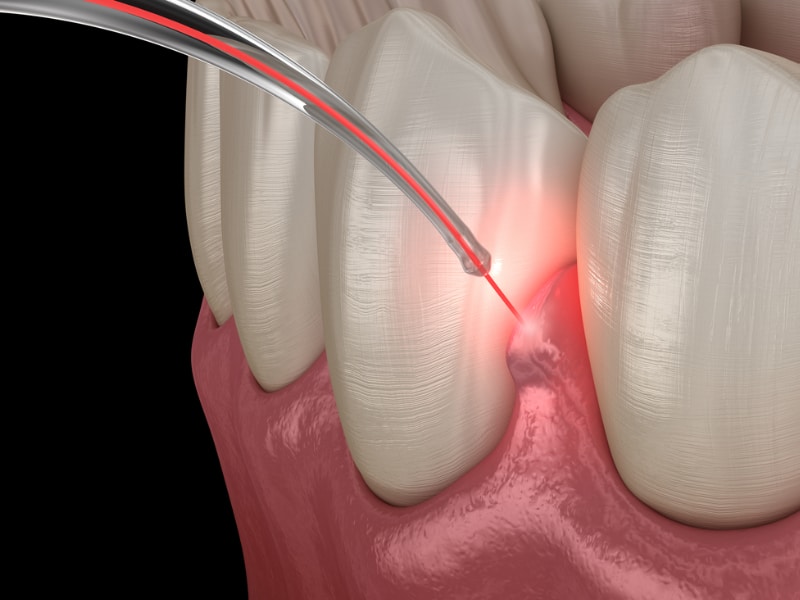

Laser u dentalnoj medicini

Laseri određene valne duljine služe kako bi rezali tkivo, vršili dezinfekciju te biostimulativno kako bi se tkivo koje se tretira laserom što prije oporavilo.